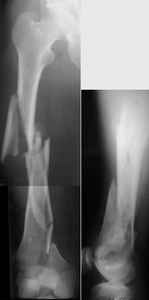

A new toy is more interesting and fashionable. And anyway it is not panacea, i have already seen presentations with LISS failures like the attached one presented by D.Seligson. And people also demonstrated incisions say that the method is not so LESS invasive as it supposed to be.